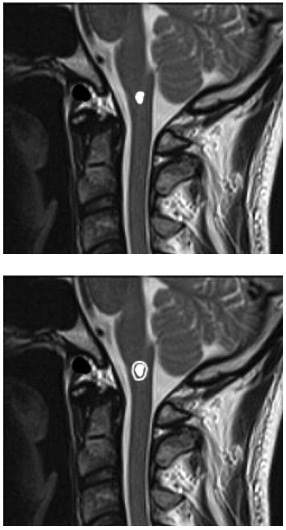

2023 B41 【問題】 50代男性。もともと下記病変(図1)を指摘されていた。1週間前から四肢麻痺、嚥下障害が出現(図2)している。適切な手術アプローチはどれか。

transcondylar approach